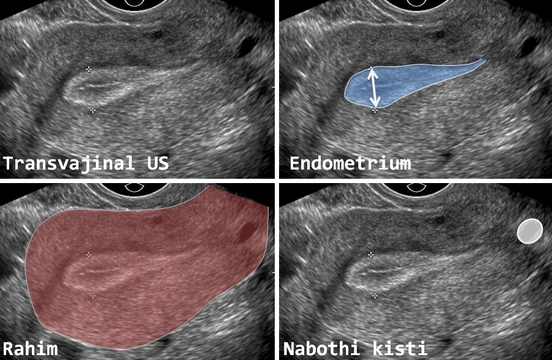

Rahim Zarı (Endometrium) Kalınlaşması Rahim zarı kalınlaşması, kadınlarda adet düzensizliği, ara kanama veya menopoz sonrası kanama gibi şikâyetlerle sıklıkla gündeme gelen önemli bir jinekolojik durumdur. Tıbbi adıyla endometrium kalınlaşması, rahmin iç yüzeyini döşeyen endometrium tabakasının, kadının yaşına ve hormonal durumuna gör...